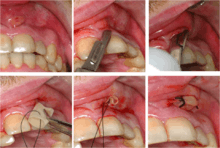

Any tooth that is identified, in either the history of pain or base clinical exam, as a source for toothache may undergo further testing for vitality of the dental pulp, infection, fractures, or periodontitis. These tests may include:[9]:10–19

- Pulp sensitivity tests, usually carried out with a cotton wool pledget sprayed with ethyl chloride to serve as a cold stimulus, or with an electric pulp tester. The air spray from a three-in-one syringe may also be used to demonstrate areas of dentin hypersensitivity. Heat tests can also be applied with hot Gutta-percha. A healthy tooth will feel the cold but the pain will be mild and disappear once the stimulus is removed. The accuracy of these tests has been reported as 86% for cold testing, 81% for electric pulp testing, and 71% for heat testing. Because of the lack of test sensitivity, a second symptom should be present or a positive test before making a diagnosis.

- Radiographs utilized to find dental caries and bone loss laterally or at the apex.

- Assessment of biting on individual teeth (which sometimes helps to localize the problem) or the separate cusps (may help to detect cracked cusp syndrome).

Less commonly used tests might include trans-illumination (to detect congestion of the maxillary sinus or to highlight a crack in a tooth), dyes (to help visualize a crack), a test cavity, selective anaesthesia and laser doppler flowmetry.

Pulp sensibility test using ethyl chloride (cold stimulus)

Electric pulp tester

Plastic wedge to identify pain on biting from a fractured tooth

Transillumination demonstrating fracture

Decay (green) with apical abscess (blue)

Gutta-percha point indicating abscess origin